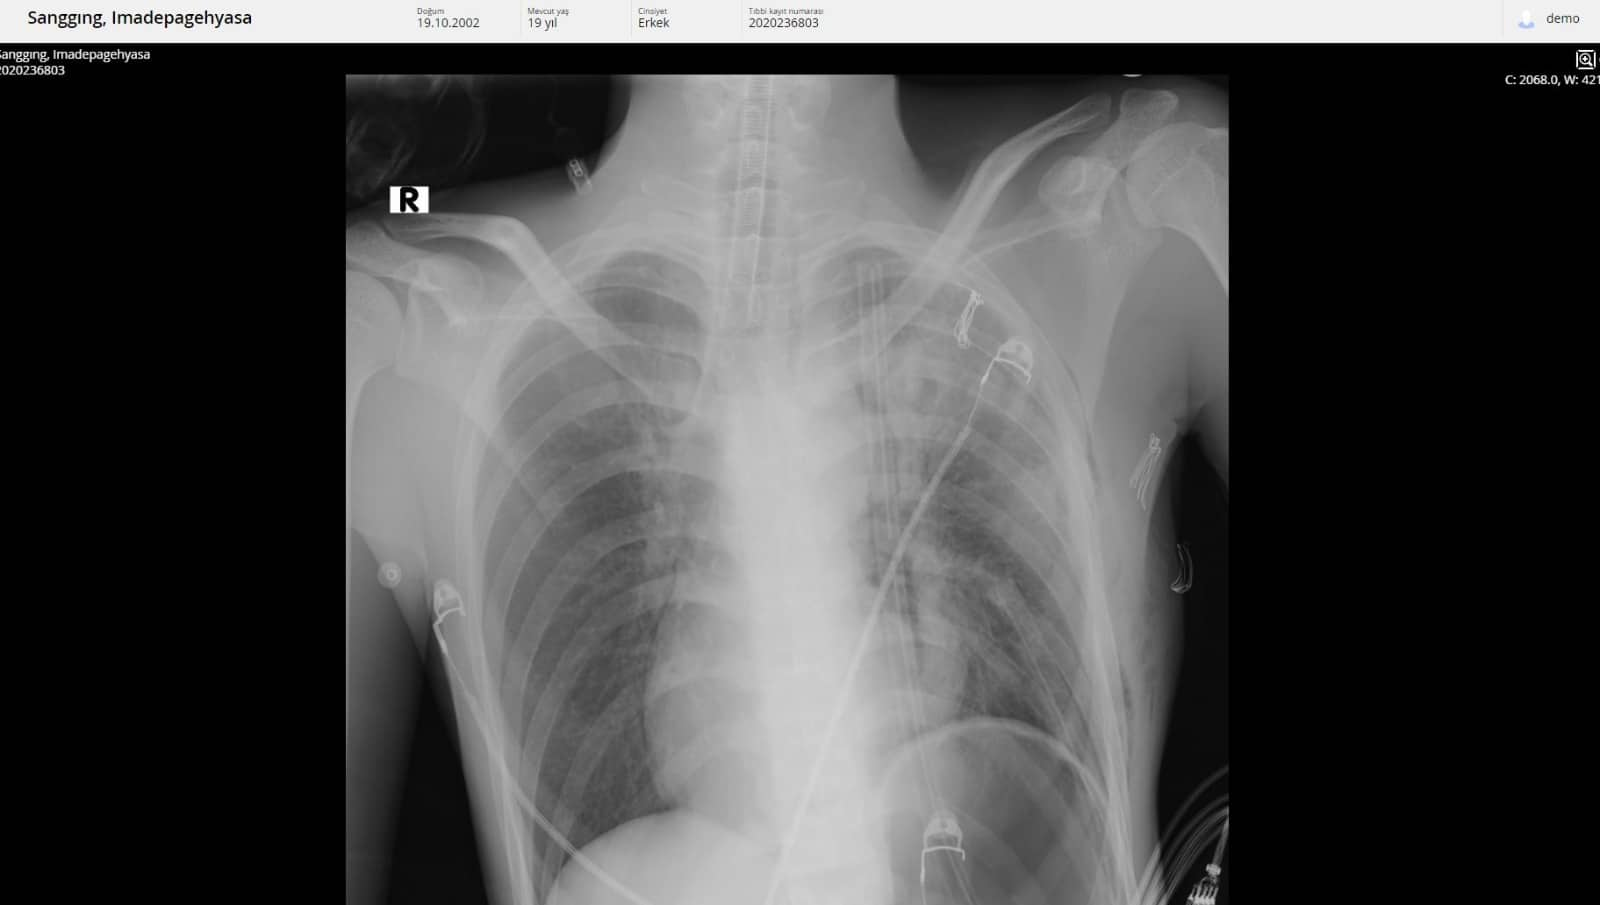

Tatil için Alanya’ya gelen 19 yaşındaki Endonozyalı I Made Pagehyasa Sanggıng, ağzından öksürükle birlikte kan gelmesi şikâyetleri ile Alanya Eğitim ve Araştırma Hastanesi Acil Servise başvurdu. Yapılan tetkik ve görüntülemeler neticesinde Sanggıng’ın sağ akciğerin tamamen fonksiyon dışı kalmasına yol açan bir kitle tespit edildi.

Kitlenin ayrıca kalbe ve diğer hayati organlara da ciddi bir baskı oluşturduğu belirlendi. 19 yaşındaki hasta ALKÜ Tıp Fakültesi Göğüs Cerrahisi Anabilim Dalı Başkanı Dr. Öğretim Üyesi Oktay Aslaner tarafından acil ameliyata alındı. Başarılı geçen operasyon sonunda hasta yeniden sağlığına kavuştu. Eski sağlığına kavuşan I Made Pagehyasa Sanggıng’ın ilk ziyaretçisi doktoru oldu.

Dr. Aslaner operasyon hakkında bilgi vererek şunları söyledi: “Acile başvuran Endonezyalı hastamızda tetkikleri sonucunda sağ göğüs kafesinin içinde dev bir kitle tespit edildi. Kalbi tamamen karşı tarafa itmiş, sol akciğerin ana atar damarını nerdeyse kapatmış şekildeydi. Ekibimle birlikte ameliyata aldık. Ameliyatta sağ göğüs kafesinden iki akciğer arasında köken alan ve sol hemotoraksı dolduran 3 kilo ağırlığında bir kitle çıkardık. Sonrasında hastanın akciğeri açıldı, kalbi rahatladı, akciğer atar damarı normal hale geldi. Kitlenin tamamen çıkarılmasıyla birlikte hasta yeniden sağlığına kavuştu. İlerleyen tıbbi cihazlar ve hastanemizdeki yoğun bakım olanakları bu tür ilerlemiş tümörlere müdahale imkânı sağlamaktadır” dedi.